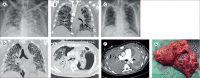

Findings: Between May 1 and Sept 30, 2020, 12 patients with COVID-19-associated ARDS underwent bilateral lung transplantation at six high-volume transplant centres in the USA (eight recipients at three centres), Italy (two recipients at one centre), Austria (one recipient), and India (one recipient). The median age of recipients was 48 years (IQR 41-51); three of the 12 patients were female. Chest imaging before transplantation showed severe lung damage that did not improve despite prolonged mechanical ventilation and extracorporeal membrane oxygenation. The lung transplant procedure was technically challenging, with severe pleural adhesions, hilar lymphadenopathy, and increased intraoperative transfusion requirements. Pathology of the explanted lungs showed extensive, ongoing acute lung injury with features of lung fibrosis. There was no recurrence of SARS-CoV-2 in the allografts. All patients with COVID-19 could be weaned off extracorporeal support and showed short-term survival similar to that of transplant recipients without COVID-19.